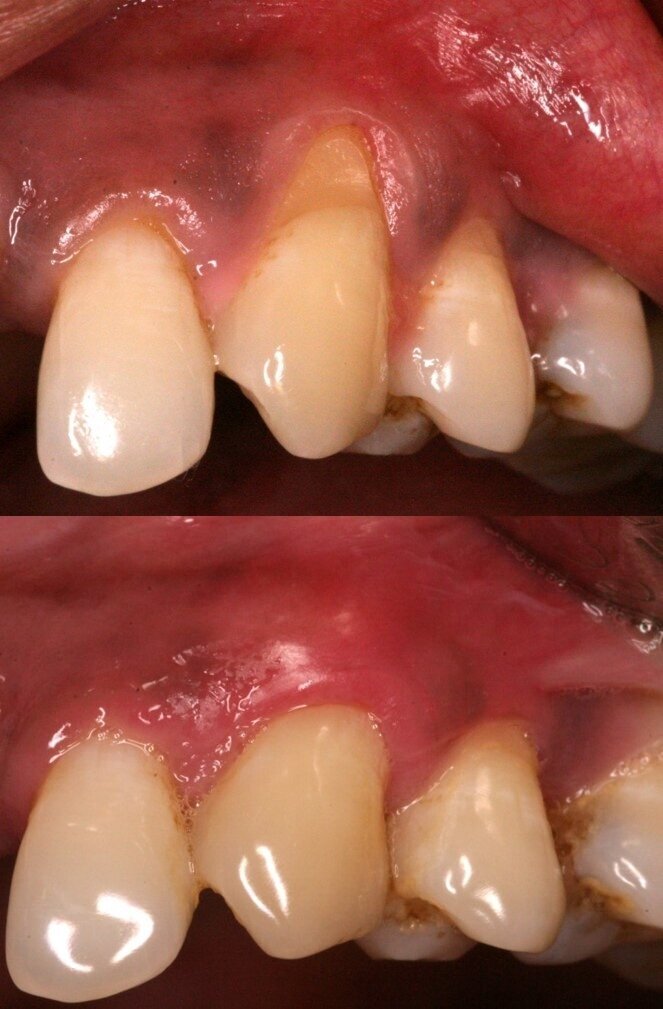

Our clinical assessment demonstrates that, in India, we deal with a unique situation of having patients with thin biotypes, both around teeth and around implants. As a consequence, our patients are more prone to peri-implant and periodontal gingival recession (Fig 1). If the biotype and keratinization is not taken into account at baseline, it becomes a patient management problem later to add soft tissue augmentation to the list of required procedures. In my personal opinion, I have seen about 80% of my implant cases needing either soft tissue augmentation, or hard tissue, or both.

Fig 1: Thin tissue biotype predisposes to mucogingival problems around implants and teeth

Figure 2: Baseline and 5 yr post op photos after root coverage using a CT graft. Stable long term soft tissue attachment is predictable.